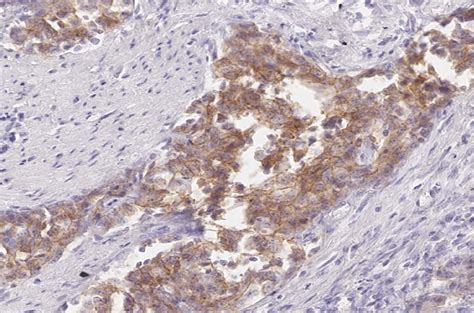

Okay, so now that we know what HER2 is and why it’s so important, let’s dive into how doctors actually test for it, focusing on that initial HER2-neu score 2 result you might have received. The first line of testing for HER2 status is typically done through a method called Immunohistochemistry (IHC) . Guys, this is a pretty standard and widely used test, and it’s usually performed on a small piece of tissue taken during a biopsy or surgery. Essentially, what happens is a pathologist—a doctor who specializes in looking at tissues under a microscope—will treat your tissue sample with special antibodies. These antibodies are designed to stick specifically to the HER2 proteins on the surface of the cancer cells. When they stick, they produce a visible color change, which the pathologist can then see. The intensity and completeness of this staining are what give us the IHC score. It’s like a visual gauge of how many HER2 antennas are present on those cells. The scoring system is fairly straightforward, ranging from 0 to 3+: A score of 0 or 1+ means there’s very little to no HER2 protein on the cells; these tumors are considered HER2-negative . A score of 3+ is the opposite end of the spectrum, indicating a very high level of HER2 protein, meaning the tumor is definitively HER2-positive . These clear-cut results make treatment decisions much simpler. However, then there’s that middle ground: the HER2-neu score of 2+ . This is what we call an equivocal result. It means the staining was present, but it wasn’t quite strong enough or widespread enough to be definitively called 3+ positive, nor was it weak enough to be considered 0 or 1+ negative. It’s like being in a gray area, where there might be overexpression, but the IHC test alone can’t give a definitive answer. This is a super important point because a 2+ score doesn’t automatically mean you’re HER2-positive and will receive targeted therapy. Instead, it signals to your medical team that more testing is needed to clarify the situation. This equivocal status is the reason why a second, more precise test is required, ensuring that no stone is left unturned in accurately characterizing your tumor. It might feel like a delay or an added complication, but trust me, it’s a necessary step to ensure you get the most accurate diagnosis and, therefore, the most effective treatment. Pathologists are highly trained to interpret these nuances, but even their expert eyes need confirmation when results fall into this indeterminate range. So, when you see that 2+ on your IHC report, know that it’s just the first chapter in your diagnostic story, not the final word. It’s a prompt for more in-depth investigation to truly understand what’s happening at the genetic level, which is where the FISH test comes into play.